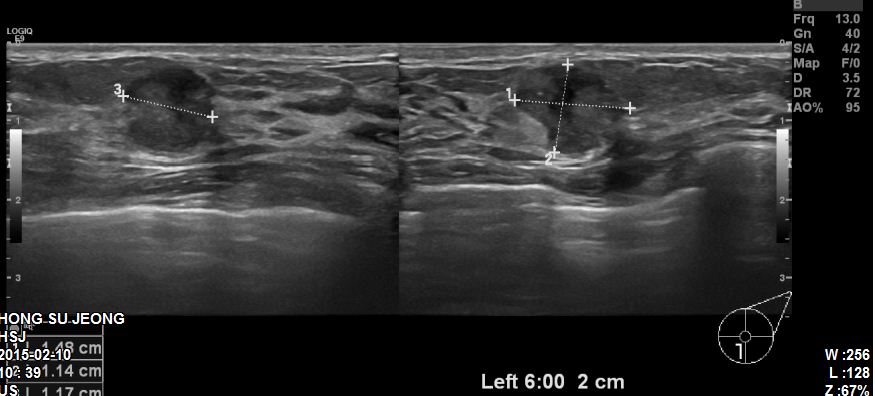

본원에 내원하신 30대 환자분이십니다.

유방초음파 후 좌측유방에 1.48cm의 혹 조직검사 시행하였고

침윤성유관암 진단되었습니다.